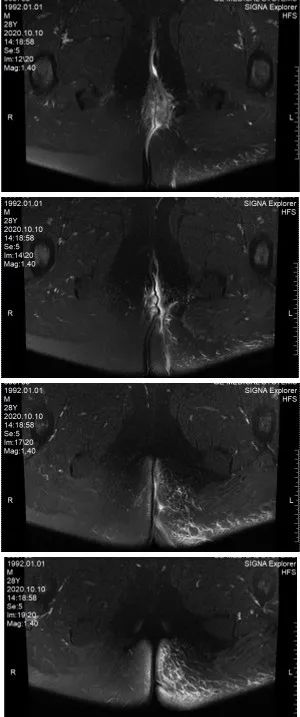

2020-09-28复查MRI